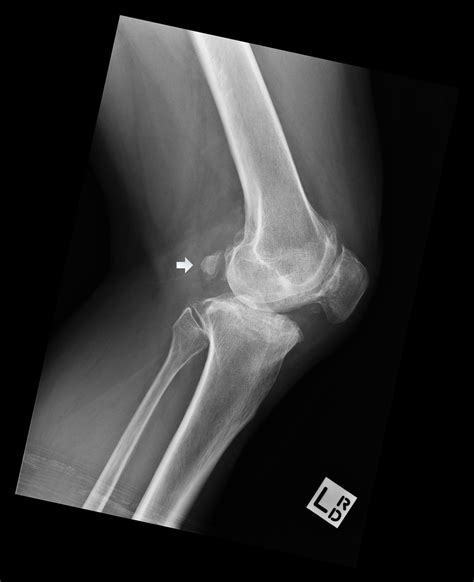

Common Conditions Diagnosed with a Lateral Knee Xray

A Lateral Knee Xray can help diagnose a variety of knee conditions. Some of the most common include:

• Fractures: Fractures of the patella, femur, or tibia can be clearly seen in a lateral view.

• Arthritis: Joint space narrowing and bone spurs can indicate osteoarthritis or other forms of arthritis.

• Patellar Dislocation: Misalignment of the patella can be diagnosed with a lateral view.

• Tibial Plateau Fracture: This type of fracture, which involves the upper part of the tibia, can be clearly seen in a lateral view.

• Soft Tissue Injuries: While not always visible, soft tissue injuries can sometimes be inferred from the presence of joint effusion or other indirect signs.